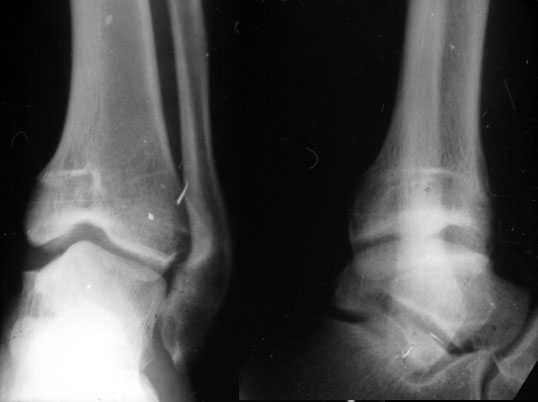

Скорее это перелом пилона 43В

> сегодняшние снимки. Главный вопрос : что делать?

Оперировать. Остеотомия, исправлять ось. Вопрос чем фиксировать? Зависит от того, чем владеете, что у вас есть в отделении, что может себе позволить пациент.

Я бы фиксировал пластинами LCP: 1\3 трубки на м\б и метафизарную 3,5/4,5/5,0 или DMT на б\б...

Но можно гвоздем, можно и аппаратом...